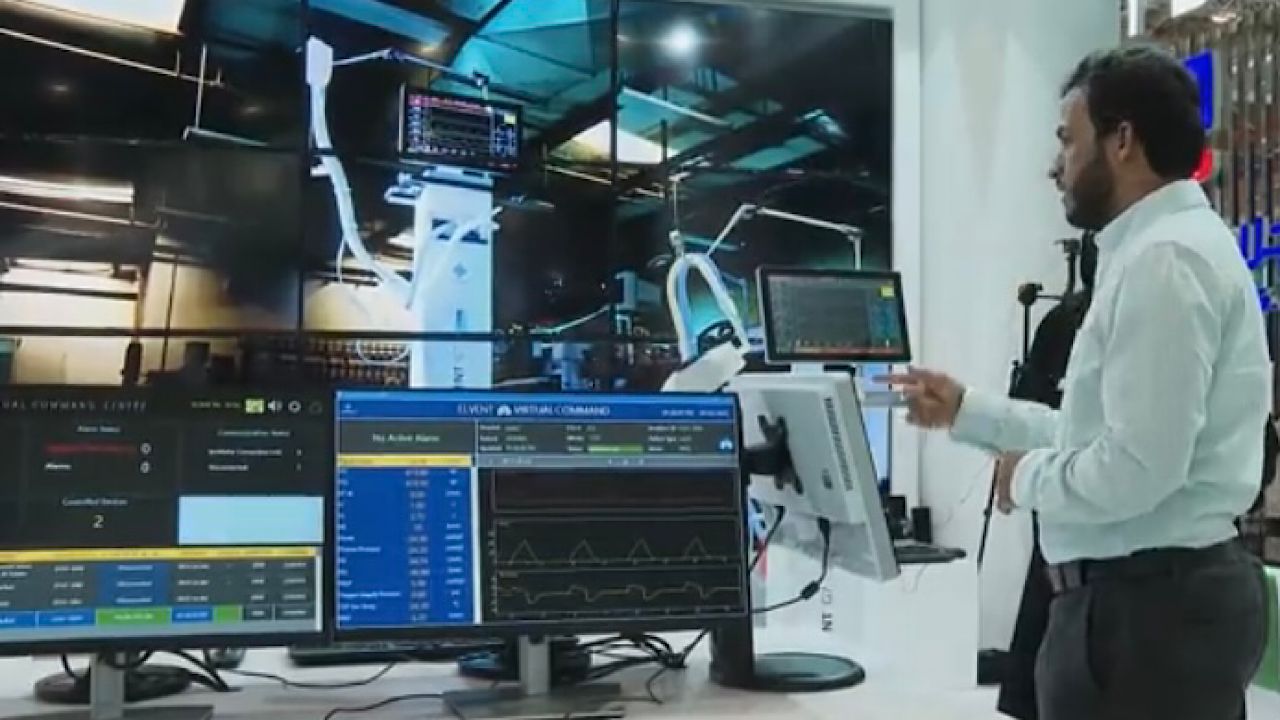

بالفيديو.. جهاز تنفس صناعي مبتكر محليًا بقدرات نوعية وتقنيات حديثة